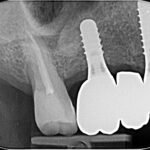

Intelligenza artificiale per la diagnosi precoce e la previsione di complicanze perimplantari Premium

La gestione delle complicanze peri-implantari rappresenta una sfida importante nell'ambito dell'implantologia moderna. La rilevazione precoce e la previsione di queste problematiche sono cruciali per un intervento tempestivo ed efficace. Le tecnologie di intelligenza artificiale (IA), in particolare il machine learning (ML) e il deep learning (DL), hanno mostrato un ottimo potenziale nell’automazione della rilevazione, nell’integrazione di dati multimodali e nel supporto alle decisioni cliniche.

Chirurgia guidata: strumento indispensabile nella pianificazione chirurgica e protesica

In questo case report realizzato dal Dott. Gabriele Vaccaro, viene descritto un intervento di riabilitazione implantare di un dente singolo effettuato con pianificazione digitale....